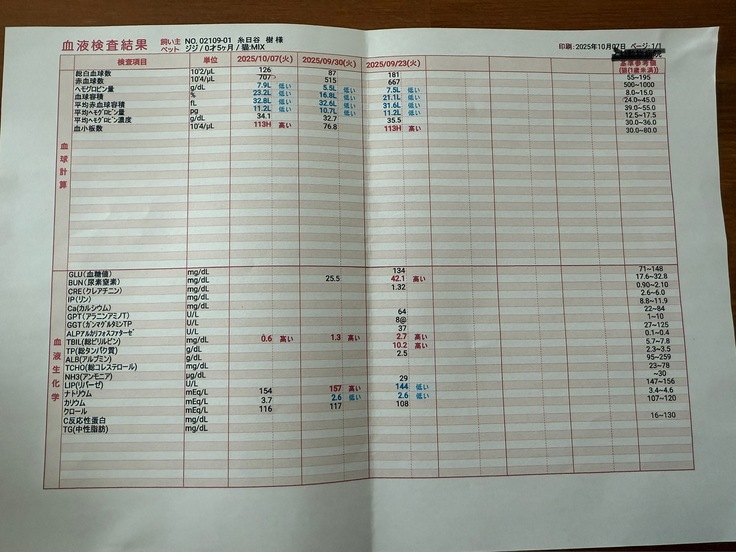

すぐに血液検査など詳しい検査をしていただき、出た結果です。

タンパク質からの計算式に基づいて、この時点でおそらくFIPで間違いないだろうとの診断でした。

検査をし、ありがたいことに検査結果は良好で腎臓や黄疸の値もものすごく下がっていました。

驚くことに結果はとっても良好で、全ての値がほぼ正常値まで戻っていました。